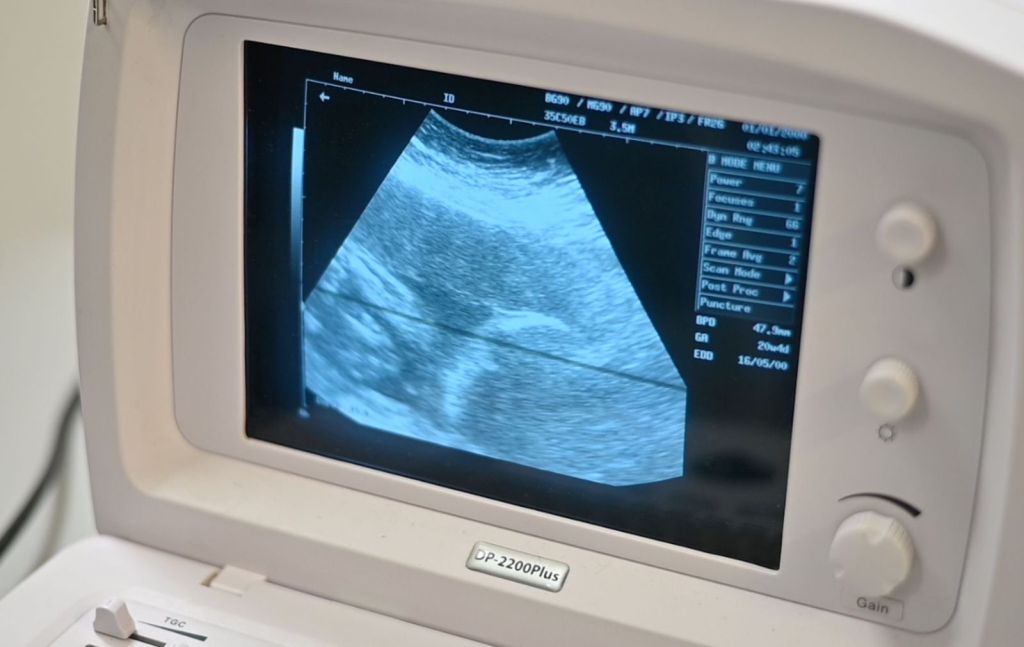

Indicó que una vez iniciado el control, se realizan una serie de tamizajes que deben de realizarse durante la gestación, con la finalidad de prevenir enfermedades como preeclampsia, diabetes o evitar hemorragias, “les brindamos mucha educación para la salud y poder llevar un embarazo saludable; así como técnicas para poder tener un parto sano, y los primeros cuidados en el recién nacido”.

En relación a las pruebas realizadas, la pasante Aranza Ortiz destacó que son practicadas pruebas de VIH y de Sífilis, que pueden atraer alguna complicación durante el embarazo, “y dependiendo el seguimiento a la paciente, se les piden estudios de laboratorio para ver algún riesgo; les controlamos la glucosa para evitar la diabetes gestacional, así como la presión arterial”.